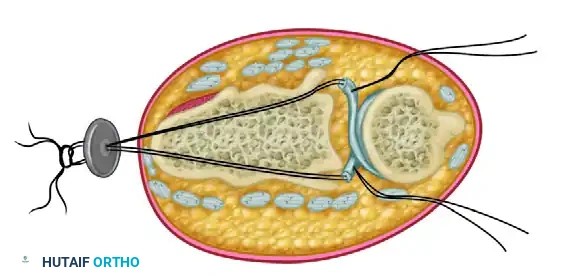

* Drill holes are created in the ulnar aspect of the distal radius.

* The free ends of the tendon graft are passed through the radius to secure the ulnar loop, effectively tethering the ulna to the sigmoid notch.

Figure: Cross-section of the wrist demonstrating the method of attaching the tendon graft through the radius.

Step 2: Tendon Routing

* A robust graft (such as fascia lata or a free tendon) is passed in a figure-of-eight or box configuration through the drill holes.

* This routing mimics the anatomic vectors of the native dorsal and volar radioulnar ligaments.

Figure: Method of passing the tendon graft through the radius and ulna to recreate the radioulnar ligaments.